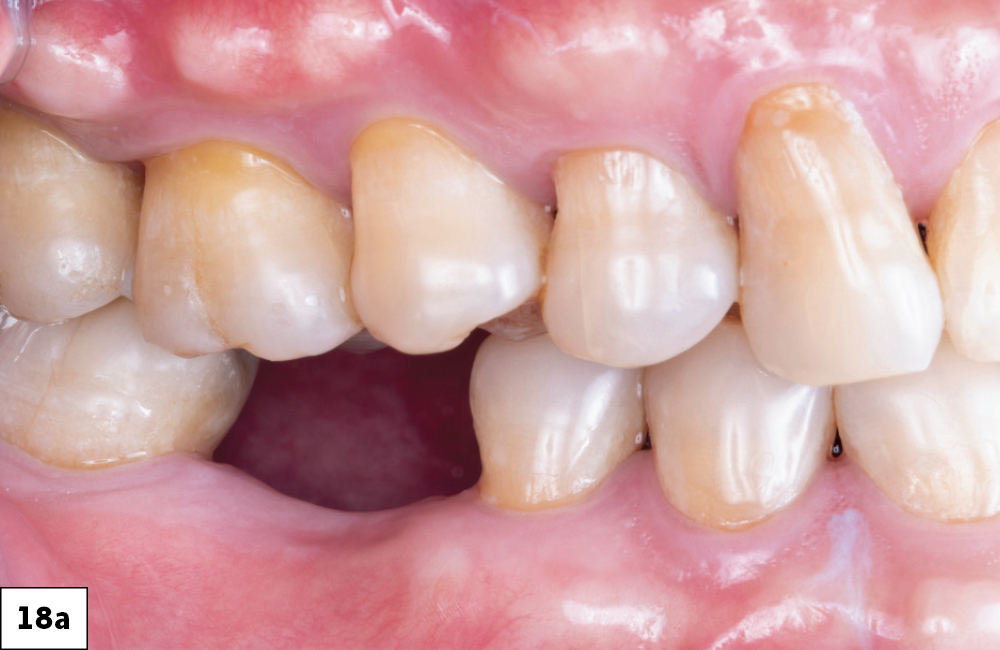

Before Restoration

After Restoration

Figures 18a, 18b: The final restoration seated perfectly without the need for any adjustment. The custom healing abutment created an emergence profile that allowed the final restoration to blend seamlessly with the adjacent teeth and appear to emerge from the tissue like a natural tooth. The result blends well with the adjacent dentition, restoring both function and esthetics.